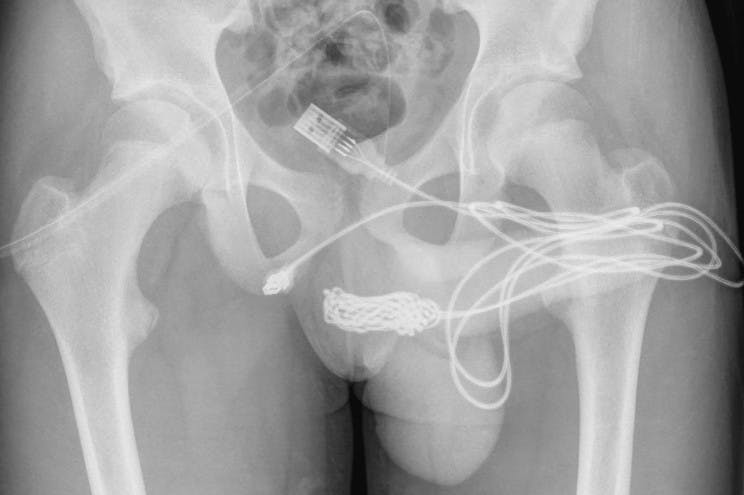

Foto: Urology Case Reports, Lægerne var nødsaget til at klippe kablet over for at fjerne det.

På dette hospital lykkedes det lægerne at fjerne USB-kablet fra den 15-årige, efter de klippede kablet over, og herefter fjernede delene fra drengens lem.